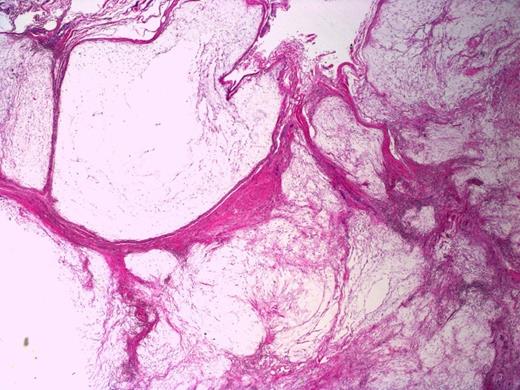

Ultrasound scan prior to referral suggested a complex mass with solid and cystic components. MRI scan demonstrated (Figure 1 and 2) the mass to be mixed fibrous and cystic components reported by a radiologist to be either fibromatosis or a desmoid tumour. The lesion was closely positioned to the Metacarpophalangeal joint but not invading the capsule. There was no sign of osteoarthritis of the joint. A marginal excisional biopsy was performed utilizing a Bruner incision. A firm fibrous mass was found with pale coloured tissue with cystic spaces containing ganglion like jelly. The mass easily reflected off the subcutaneous dermis but deep was intimately related to the palmar fascia. The radial digital nerve and vessels were separate to the mass and preserved. The wound healed well without complication. Histopathological analysis showed an irregular mass of fibrous tissue and pale mucoid material measuring 34 x 25 x 15 mm. There were multiple cystic areas containing mucoid material. (Figure 3)

Multicystic appearance of the lesion with fibrous septa. H&E stain, 20X magnification